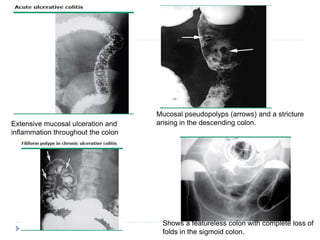

Double contrast barium enema

 May be normal in mild UC

 Diffusely reticulated pattern with superimposed punctate

collections of barium in microulcerations.

 More severe disease :- spiculated collar button ulcers, shortening of

the colon, loss of haustrae, narrowing of the luminal caliber,

pseudopolyps & filiform polyps.

 It should be avoided in patients who are severely ill since it may

precipitate ileus with toxic megacolon.

Extensive mucosal ulceration and

inflammation throughout the colon

Mucosal pseudopolyps (arrows) and a stricture

arising in the descending colon.

Shows a featureless colon with complete loss of

folds in the sigmoid colon.